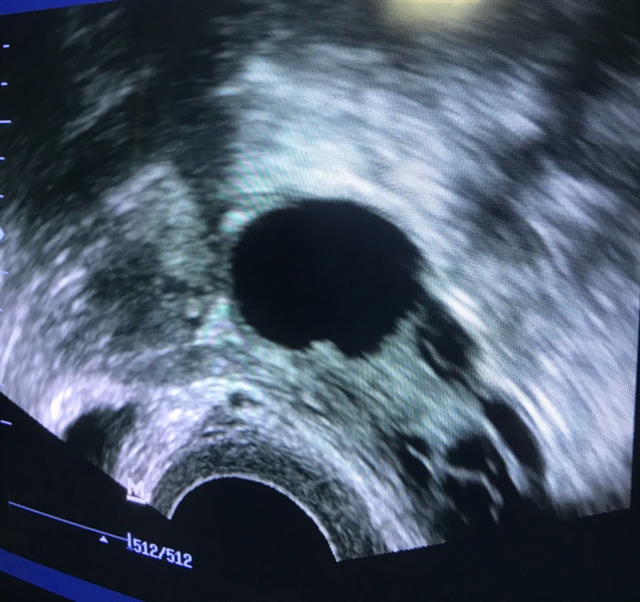

樱桃🍒喵喵鱼🐟[帖主]:可以,我们这边有些3个月以后就可以备孕,我是有很多问题 纵隔 、肌瘤、巧囊、粘连,子宫内膜异位症